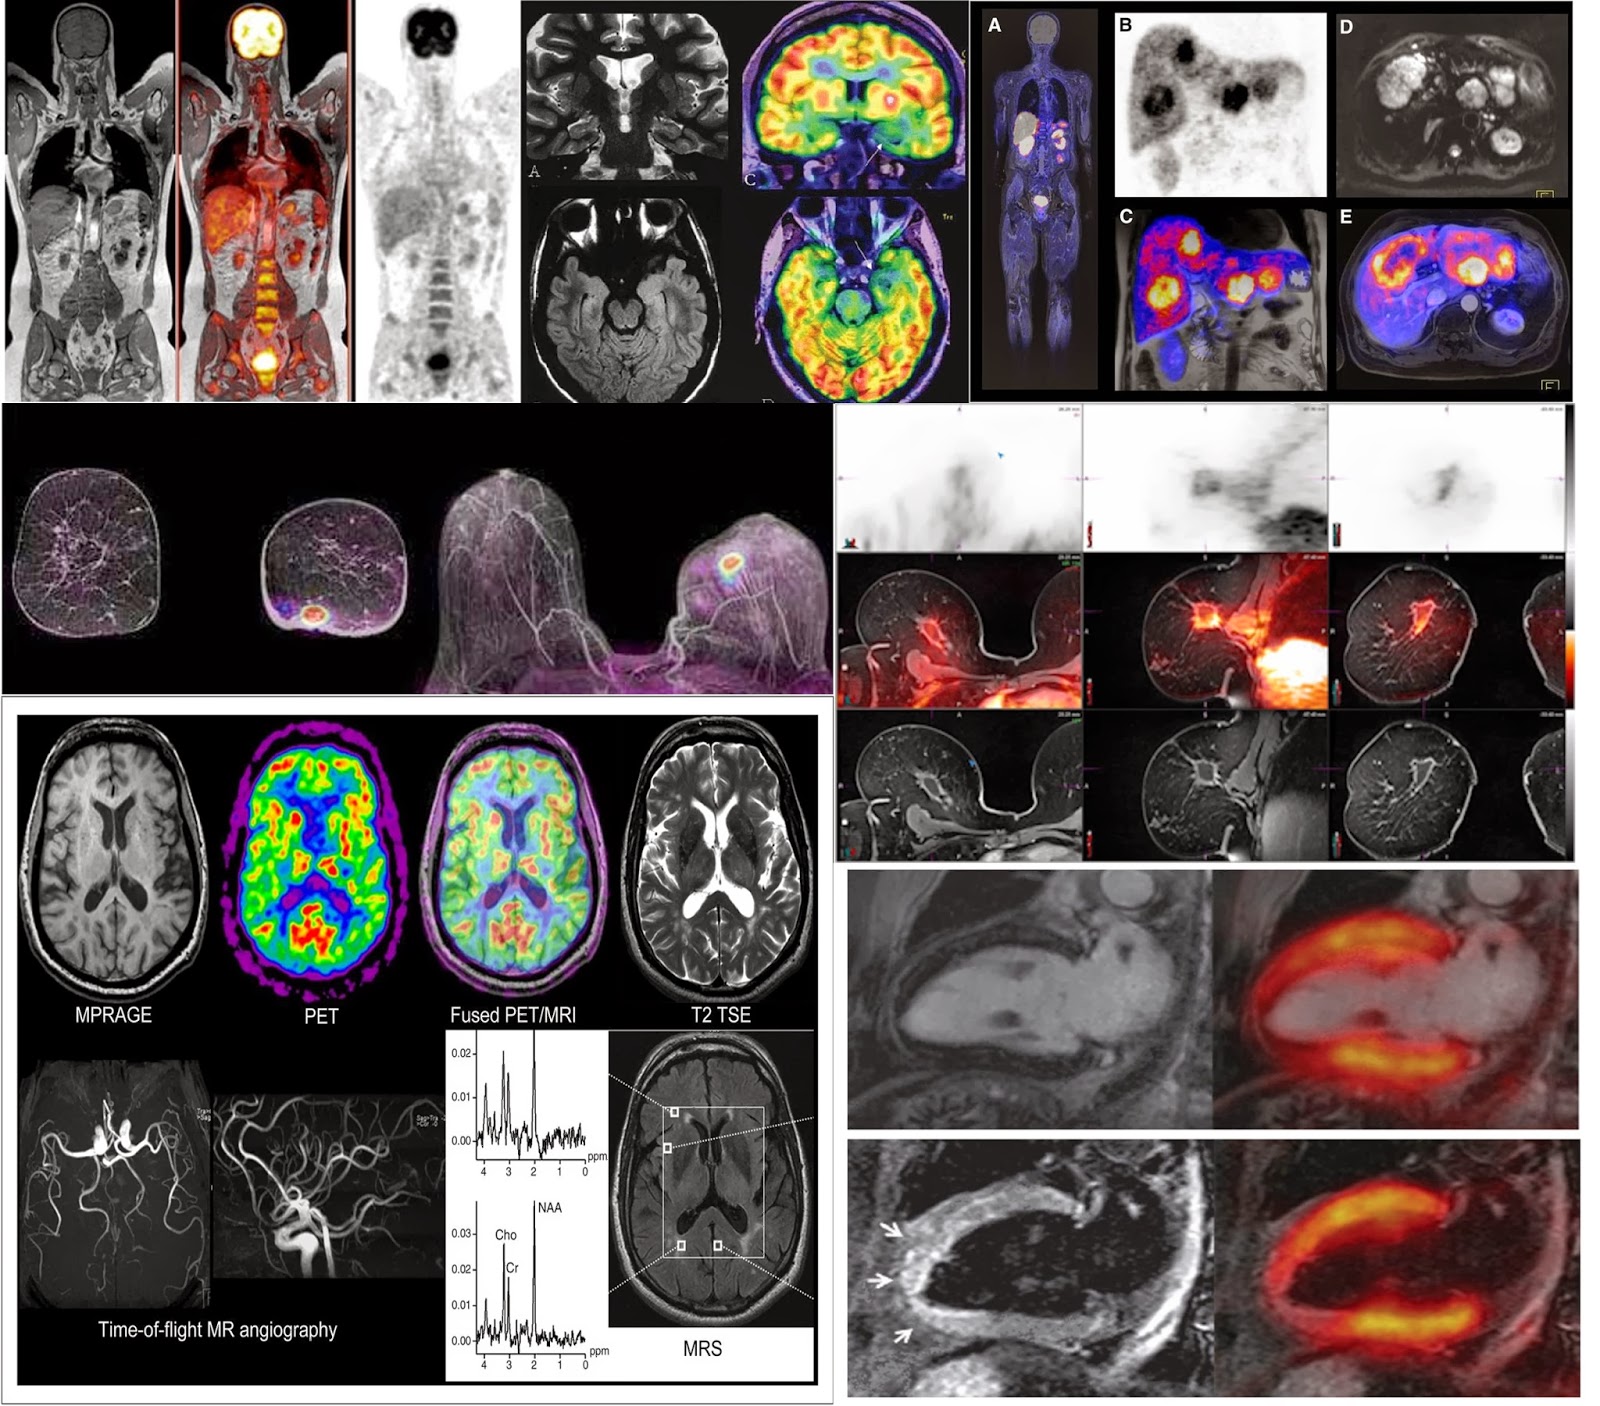

PET/CT and PET/MRI images of 56yold patient with glioblastoma What Is Pet/Mr pet/mr imaging offers the potential for a powerful “onestop shop” combination of structural, functional, and molecular imaging. Pet/ct machines have been in operation longer than pet/mri machines, which are. a positron emission tomography (pet) scan is an imaging test that can help reveal the metabolic or biochemical function of your tissues and organs. pet/ct or pet/mri? . What Is Pet/Mr.

Cardiac PET/MR imaging of a 66yearold male patient with STelevation What Is Pet/Mr Pet/ct machines have been in operation longer than pet/mri machines, which are. a positron emission tomography (pet) scan is an imaging test that can help reveal the metabolic or biochemical function of your tissues and organs. Pet stands for positron emission. the most basic pet/mr protocol consists of mr localizers to allow planning of the pet bed positions,. What Is Pet/Mr.

PET/MR imaging with BrainPET system in a volunteer. Three... Download What Is Pet/Mr pet/ct or pet/mri? the most basic pet/mr protocol consists of mr localizers to allow planning of the pet bed positions, then. Pet stands for positron emission. Pet/ct machines have been in operation longer than pet/mri machines, which are. a positron emission tomography (pet) scan is an imaging test that can help reveal the metabolic or biochemical function. What Is Pet/Mr.

First simultaneous PET/MRI study in 66yold healthy volunteer. MRI What Is Pet/Mr pet/mr imaging offers the potential for a powerful “onestop shop” combination of structural, functional, and molecular imaging. a positron emission tomography (pet) scan is an imaging test that can help reveal the metabolic or biochemical function of your tissues and organs. Pet/ct machines have been in operation longer than pet/mri machines, which are. the most basic pet/mr. What Is Pet/Mr.